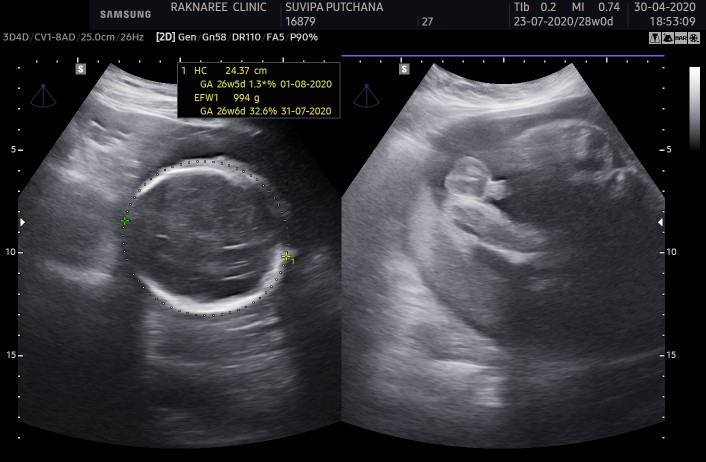

ขอดูใบซาวเด็ก ผช. ของแม่ๆ หน่อยค่ะ ?

ในภาพเป็น ผช ใช่ไหมค่ะ พอดีหมอขอชัวร์ๆ เดือนหน้า เลยสอบถามแม่ๆ ที่มีประสบการณ์ลูกชาย หน่อยค่ะ ?ขอดูใบอัตตลาซาวเด็ก ผช . หน่อยจร้าาา? ถาพไม่ชัดเพราะถ่าย VDO มาจร้า ??

ผช คะ